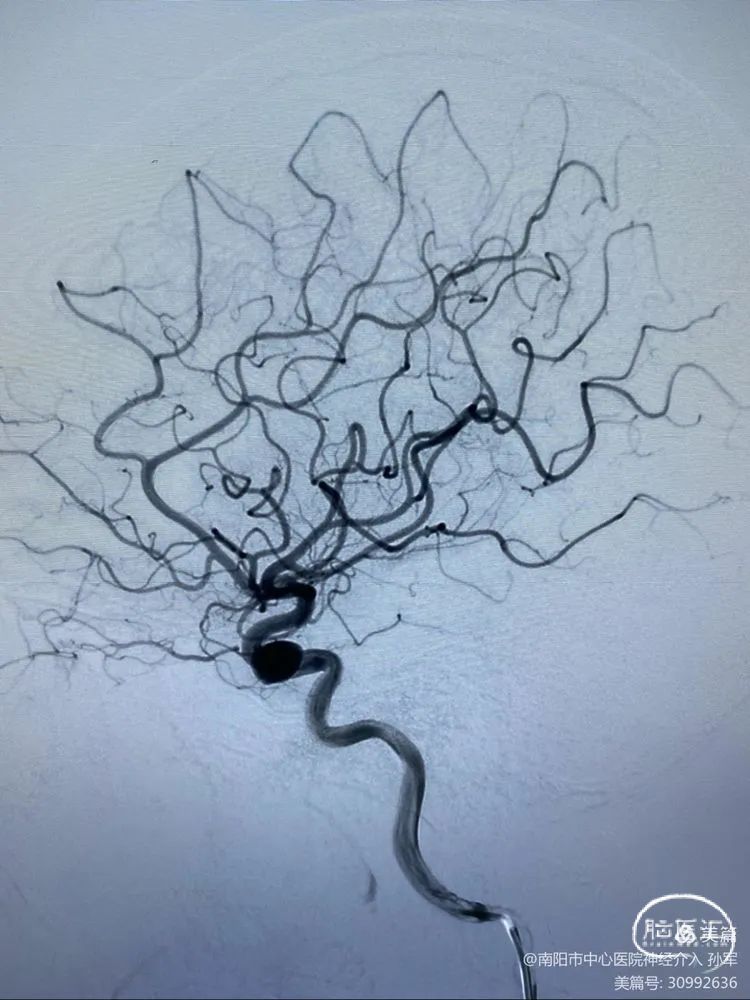

患者:女性,54岁

诊断:虹吸段大动脉瘤,瘤颈部分瘤化

手术计划:Pipeline Flex结合弹簧圈治疗

术前影像学资料